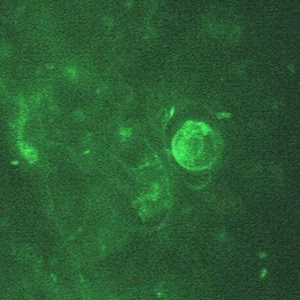

Naegleria fowleri cysts.

Naegleria fowleri does not form cysts in human tissue. Cysts in the environment and culture are spherical, 7-15 µm in diameter and have a smooth, single-layered wall. Cysts have a single nucleus.

Naegleria fowleri trophozoites.

There are two forms of trophozoites in Naegleria fowleri: ameboid and ameboflagellate, the latter of which is only rarely found in humans (within CSF). The ameboid trophozoites measure 10-35 µm but when rounded are usually 10—15 µm in diameter. In culture, trophozoites may grow to over 40 µm. The cytoplasm is granular and contains many vacuoles. The single nucleus is large and has a large, dense karyosome and lacks peripheral chromatin.